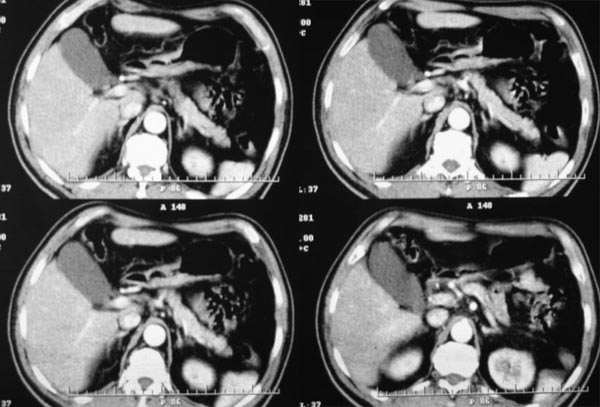

门脉期

3、门脉期:病灶呈低密度,低于肝实质,下腔静脉见充盈缺损,说明癌栓形成

2.病灶特点:平扫呈低密度,密度不均,中央呈更低密度;动脉期病灶周围强化较明显,高于正常肝组织,低于同层主动脉密度,中央坏死区未见明显强化;门静脉期,病灶呈低密度,低于正常肝组织密度。

肿瘤实质的强化特点符合肝癌表现,需要注意的地方还有患者可能存在门脉右支和下腔静脉内癌栓形成,这更加支持肝癌的诊断。

肿瘤的生长特点和强化特点符合纤维板层样肝细胞癌,下腔静脉内在动脉期有充盈缺损,而在静脉期内未见充盈缺损,故不考虑下腔静脉瘤栓形成

门脉期下腔静脉内可見充盈缺损,考虑栓塞,应考虑为恶性病变,旰癌可能性大